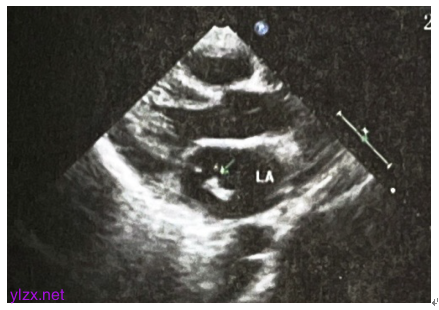

双下肢静脉彩超未见明显异常。心脏彩超示二尖瓣腱索断裂并中重度关闭不全,二尖瓣前后瓣及腱索赘生物,肺动脉增宽,轻度肺动脉高压,三尖瓣轻度反流,主动脉瓣微量反流(图2)。

图2 心脏彩超